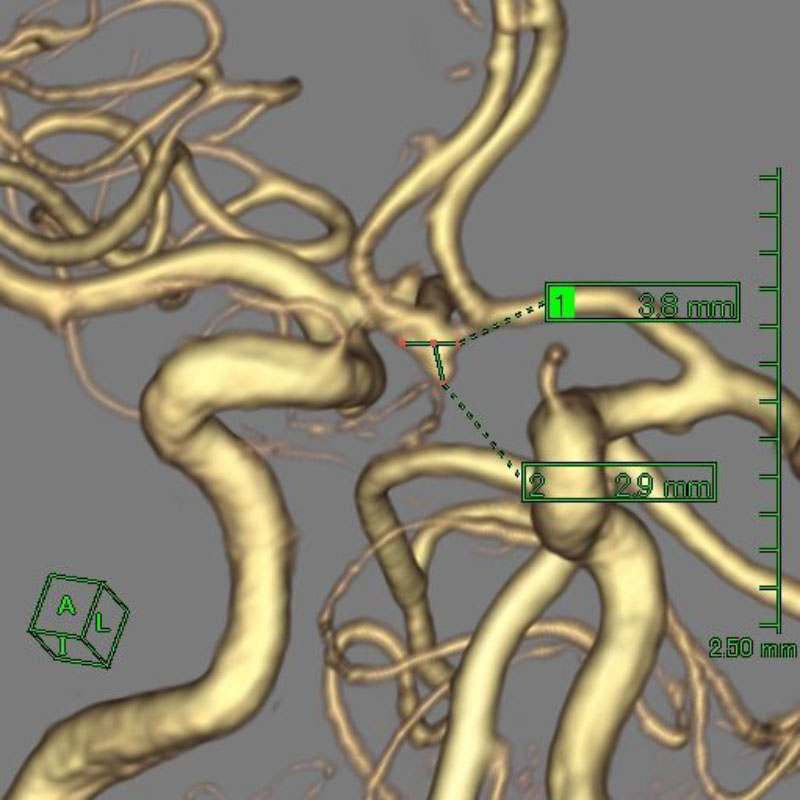

手術前

クリップ前

クリップ後

手術後